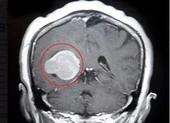

Khối u qua ảnh chụp MRI và các bác sĩ đang tiến hành phẫu thuật cắt khối u qua kính hiển vi. Ảnh: HD 1 Khối u qua ảnh chụp MRI và các bác sĩ đang tiến hành phẫu thuật cắt khối u qua kính hiển vi. Ảnh: HD 2

Khối u qua ảnh chụp MRI và các bác sĩ đang tiến hành phẫu thuật cắt khối u qua kính hiển vi. Ảnh: HD

Kết quả chẩn đoán hình ảnh cho thấy bệnh nhân bị u màng não nền sọ kích thước 7x9,5 cm. U không xâm lấn nhưng dính vào các mạch máu lớn, trong quá trình phẫu thuật dễ gây tổn thương các mạch máu gây khó khăn trong phẫu thuật.